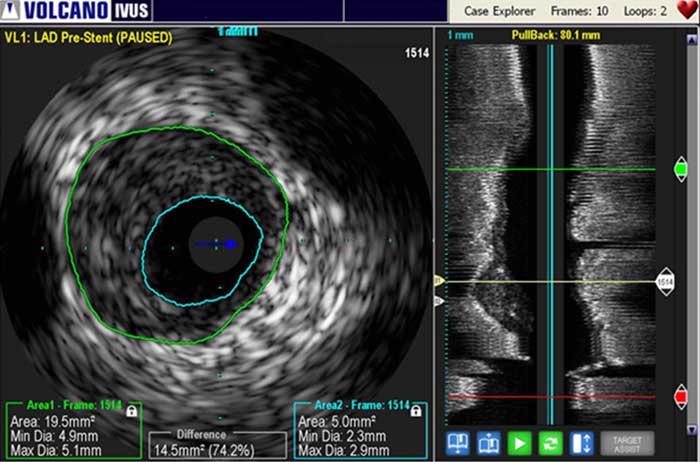

L’échographie intravasculaire (IVUS) est une technologie d’imagerie par cathéter permettant aux médecins de visualiser les vaisseaux malades depuis l’intérieur de l’artère. L’échographie intravasculaire fournit des mesures détaillées et précises de la taille de la lumière et des vaisseaux, de la surface et du volume de la plaque et de l’emplacement de repères anatomiques clés.

Une sonde d’échographie émet des ondes sonores haute-fréquence qui sont réfléchies par les parois vasculaires et renvoyées au système avec une intensité qui varie selon le tissu. L’électronique du système traite le signal pour afficher une image transversale.

L’échographie intravasculaire sert à optimiser l’implantation en vous permettant d’observer :